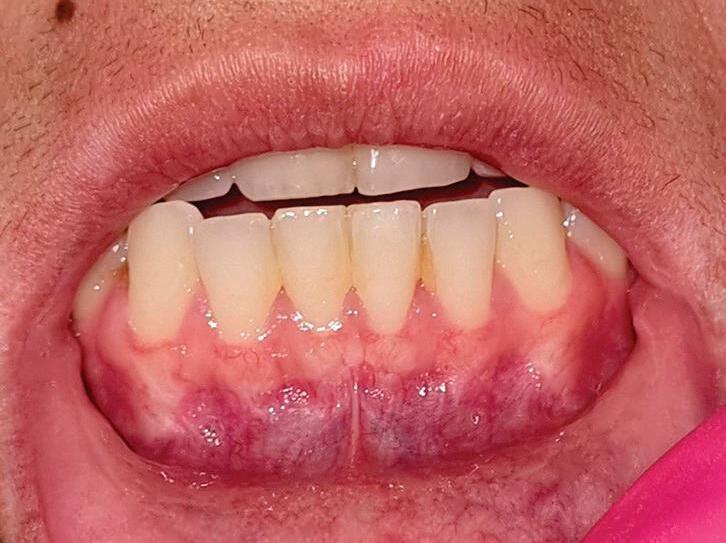

A mucosa oral que envolve os dentes, tanto em maxila quanto em mandíbula, é denominada gengiva. A gengiva marginal

posicionada entre dentes adjacentes é conhecida como papila interdental. Muitas vezes, a gengiva inserida ao osso alveolar tem regiões de pigmentação que são ditadas por raça ou etnia. A demarcação entre a gengiva inserida e a mucosa alveolar livre é a junção mucogengival (Fig. 1-3).

1-3. (a,b) Gengivas inseridas e mucosas gengivais superior e inferior. Observar mudança de textura e coloração nessas duas localizações. Observa-se também a presença dos freios labiais.